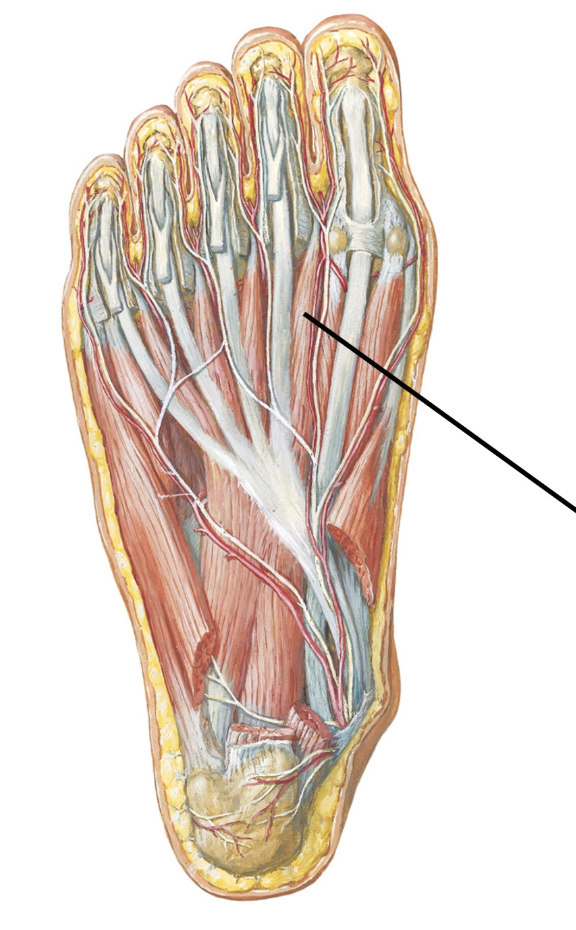

Severing this nerve would result in motor loss to which of the following muscles?

Sartorius

Paralysis of this muscle suggests injury of what named nerve?

Medial plantar nerve

What muscle would lose motor function if this nerve were severed?

Flexor digitorum brevis